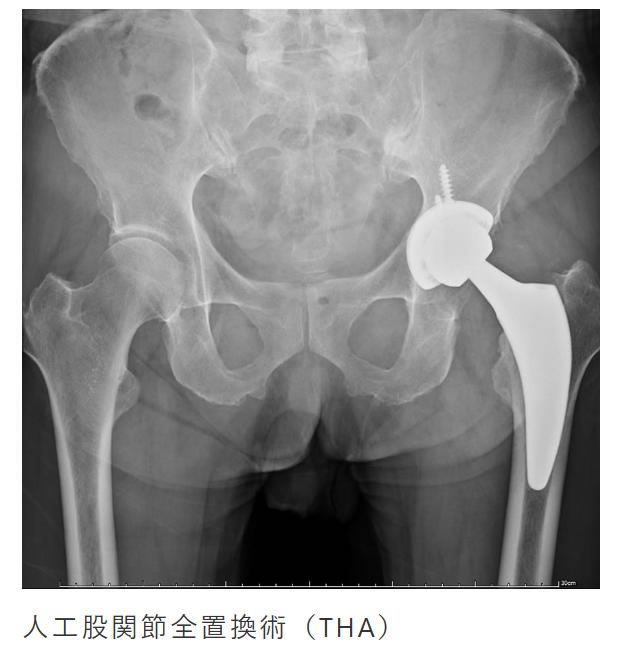

関節疾患

膝や股関節などの変形による疼痛や靭帯損傷に対して治療を行います。

変形の程度、疼痛が強い場合は人工関節置換術にて痛みの緩和を図ります。